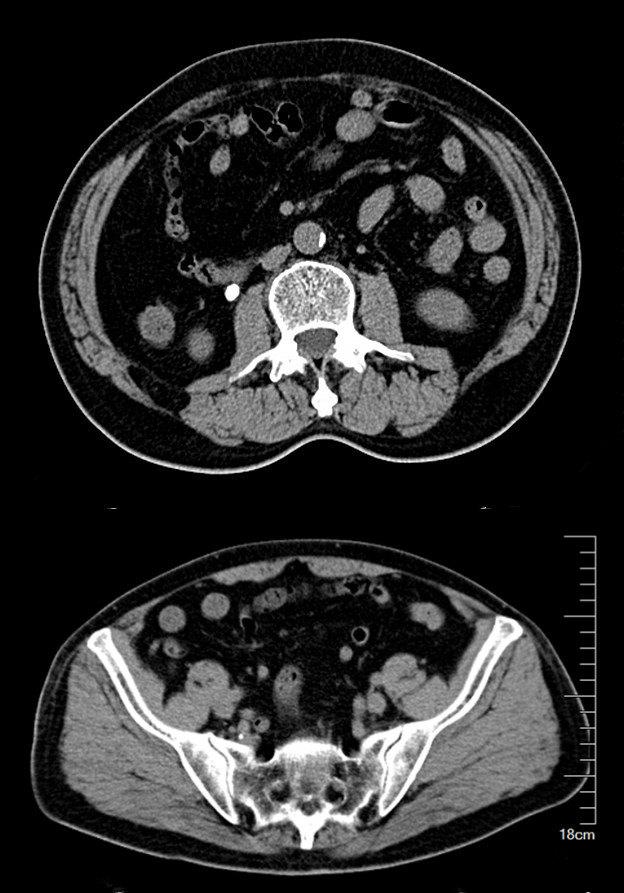

CT检查提示:右肾萎缩无功能,左侧肾脏代偿性增大,左肾积水扩张,双侧输尿管结石

2016年09月手术患者,男性,83岁,太仓人,双侧腰酸不适五年伴体检发现双侧输尿管结石一周入院,五年来患者自觉双侧腰酸,一直未予重视,近期自觉双下肢浮肿且左侧腰痛明显加剧,遂参加社区免费体检时发现双侧输尿管结石遂来院就诊,CT:右肾萎缩无功能,左侧肾脏代偿性增大,左肾积水扩张,双侧输尿管结石,左侧约1.5cm,右侧约2.0cm GFR:左侧41.27ml/min,右侧5.2ml/min。肾功能:Cr 571umol/L;术前诊断:双侧输尿管结石 右肾萎缩 右肾无功能 左肾积水,鉴于右输尿管结石梗阻时间太长,右肾已几乎无功能,萎缩固缩,且肾功能已失代偿,遂只能急症先输尿管镜处理左输尿管结石,保护左侧肾脏,待肾功能稳定后再处理右侧输尿管结石及右肾,患者预后不容乐观。